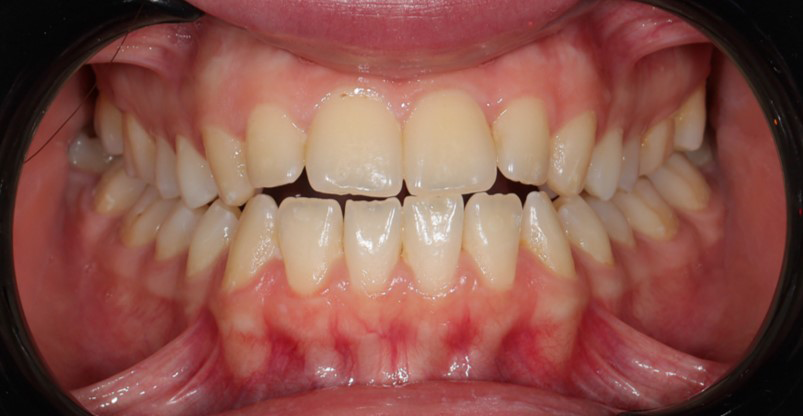

A 22-year-old female patient presented with a Class III malocclusion. She does not like her own profile. Her facial profile was straight with a slightly retrusive maxilla, the upper incisors were within normal inclination, and the lower incisors were retroclined. Bolton discrepency is on mandible for 6 teeth. A retruded upper lip and a normally positioned lower lip were noted. There was also a marked lack of midface support, and the constricted dental arches resulted in a narrow smile and pronounced dark buccal corridors.

At the end of treatment, the patient’s occlusion was corrected to Class I molar and canine relationships with a physiological overjet and overbite. Irregularities in both arches were eliminated, arch forms were coordinated, and incisor torque was effectively controlled to position the roots centrally within the alveolar bone, enhancing stability. Satisfactory intercuspation was achieved in both the anterior and posterior segments, with maintenance of midline coincidence and periodontal health throughout treatment. The case was finished and transitioned into the retention phase using fixed retainers in the maxillary and mandibular anterior regions.